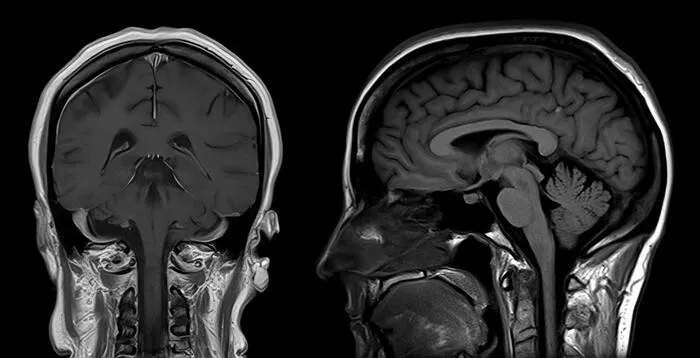

Tanısı sıklıkla klinik muayene ile konur. Ancak afazi tipini belirlemek için ayrıntılı dil beceri testleri ve ileri nöropsikiatrik değerlendirmeler gerekir. Bununla birlikte nedeni ortaya koyabilmek için beyin görüntüleme tetkikleri (MRG), ya da fonksiyonel MRG tetkikleri tanı için başvurulabilecek ileri inceleme yöntemleridir.